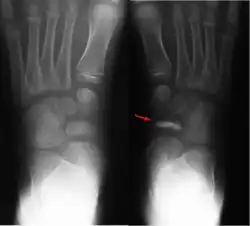

Im Röntgenbild imponieren eine scheibenförmige Verschmälerung und eine zunehmende Knochendichte im Os naviculare. Ein schollenförmiger Zerfall des Knochens ist möglich. Weiterhin besteht eine Gelenkspaltverbreiterung zwischen Talus und Os naviculare.